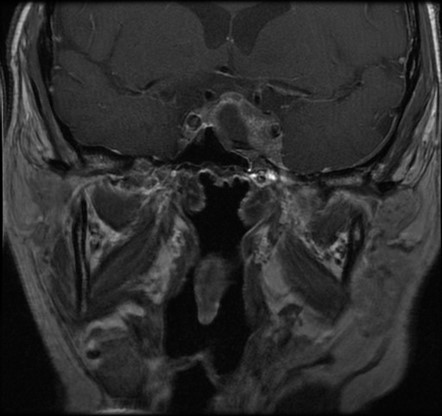

54-year-old man with weight gain and muscle weakness

Results of MRI of the pituitary gland return and are shown:

Which of the following is a correct interpretation of the MRI of the pituitary gland? (Please select only one option.)